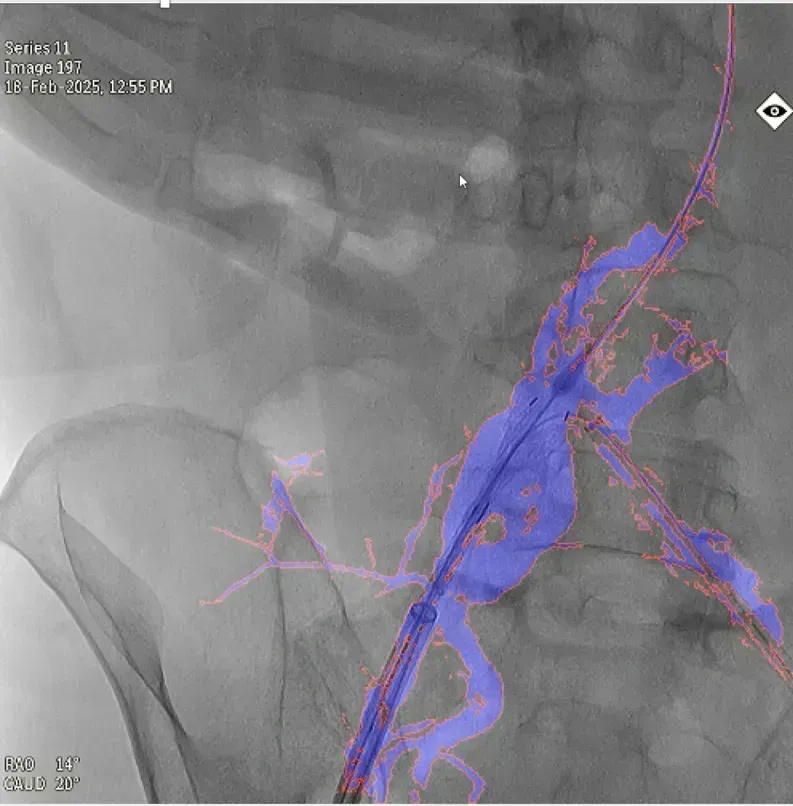

图2 本研究案例,使用10ml造影剂一次造影,实现EVAR术中髂内动脉重建,图中蓝色部分为造影显示的真实血管,红色边框为图像分割结果,融合图像的透明度可调节,与真实血管完全贴合,血管、器械的细节都清晰可见。